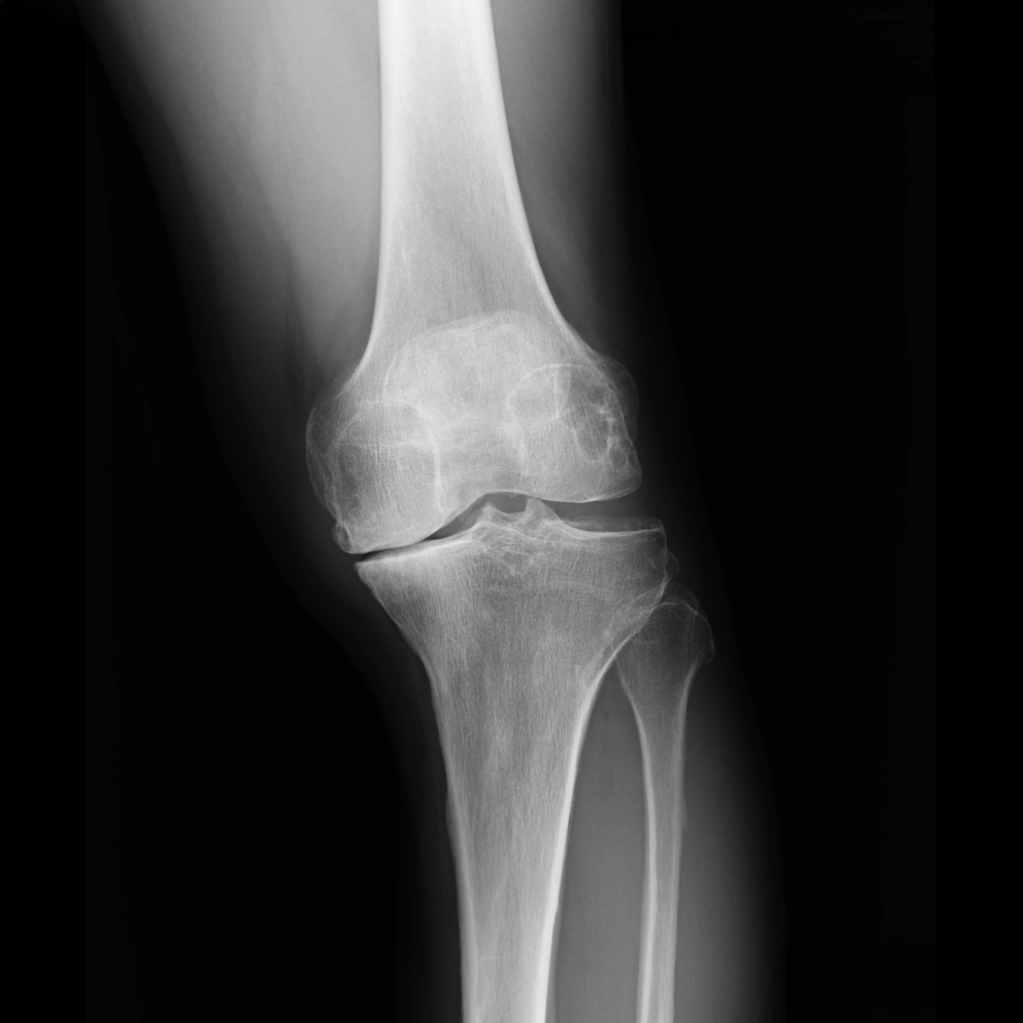

1. レントゲンの見方

ひざ関節は、大腿骨と脛骨の間の隙間の部分です。レントゲンではこの部分が隙間として写りますが、実際には関節軟骨と半月板が存在します。立位で体重をかけて撮影した場合、この隙間の広さがおおよそ関節軟骨の厚みを示すと考えてよいでしょう。この大腿骨と脛骨の隙間のうち、腓骨に近い側を外側関節、腓骨から遠い側を内側関節と呼びます。また、脛骨の中央には2つの小さな山のような部分が見えますが、ここには前十字じん帯と後十字じん帯がついています。

初期

中期

末期

※レントゲン画像左が内側、右が外側

O脚変形がみられる場合、初期のレントゲンでは外側関節に比べて内側関節の隙間がやや狭くなっています。これは内側の軟骨が少し減ってきた状態を示しています。

中期のレントゲンでは、内側関節の隙間がほとんどなくなります。この段階では、内側の軟骨が完全に失われ、大腿骨と脛骨が直接ぶつかっている状態です。低い椅子から立ち上がる際にゴリゴリという音がしたり、骨表面に髪の毛ほどの細いひび(微小骨折)が生じて強い痛みを感じるようになります。この中期変形性関節症の時期になると、痛みのために歩くのがつらくなる方が多くなります。

中期以降になると、痛み止めの薬を常用する方も増えてきます。痛みとは、ひざが脳に“骨が割れた”と知らせるシグナルであり、脳はそれを受けて修復のための炎症反応を起こし、血液を送って自己修復を始めます。ところが、痛み止めでそのシグナルを抑えたまま歩き続けると、関節の変形が進行して末期に至ることがあります。

末期では、脛骨がすり減り、大腿骨がめり込んだ状態になります。ここまで変形が進むと、ひざの中にある4つの靱帯のバランスも悪くなり、歩行が不安定になってしまいます。